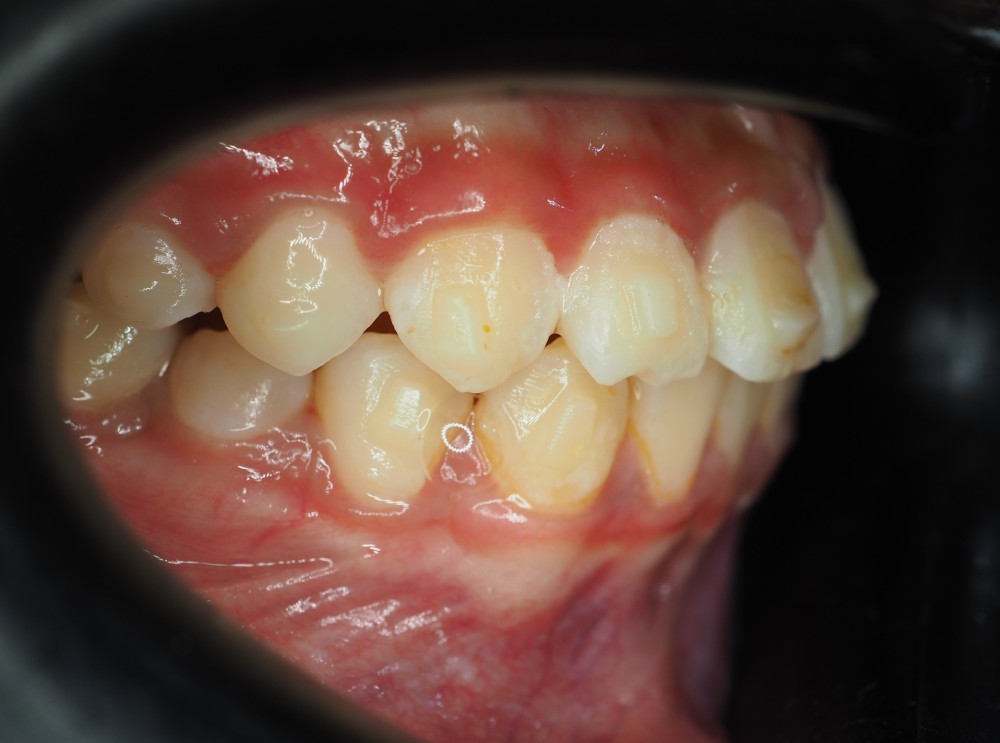

Case Study 2

Upper jaw growth → Corrected reverse bite

Age

9 years old

Parent Concern

“Her lower jaw covering upper jaw, how can Dr help with this?”

Clinical observation

Upper jaw is under-developed.

Treatment Approach

Promote mid face growth (Clear Aligner + facemask)

Treatment Outcomes

Her reverse bite was corrected in just a few months! 😁

Before (March 25)

After (Sep 25)